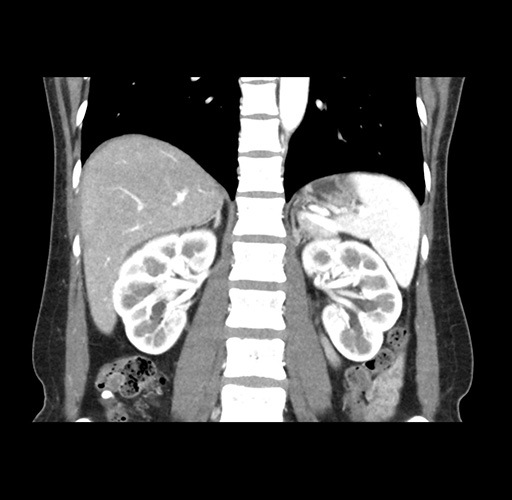

Imaging Analysis

Look through the patient's CT scan to identify any areas of concern for the necessary procedure.

Based on your CT findings, which issue(s) would give reason for "planned slowing down moment(s)" in this case?